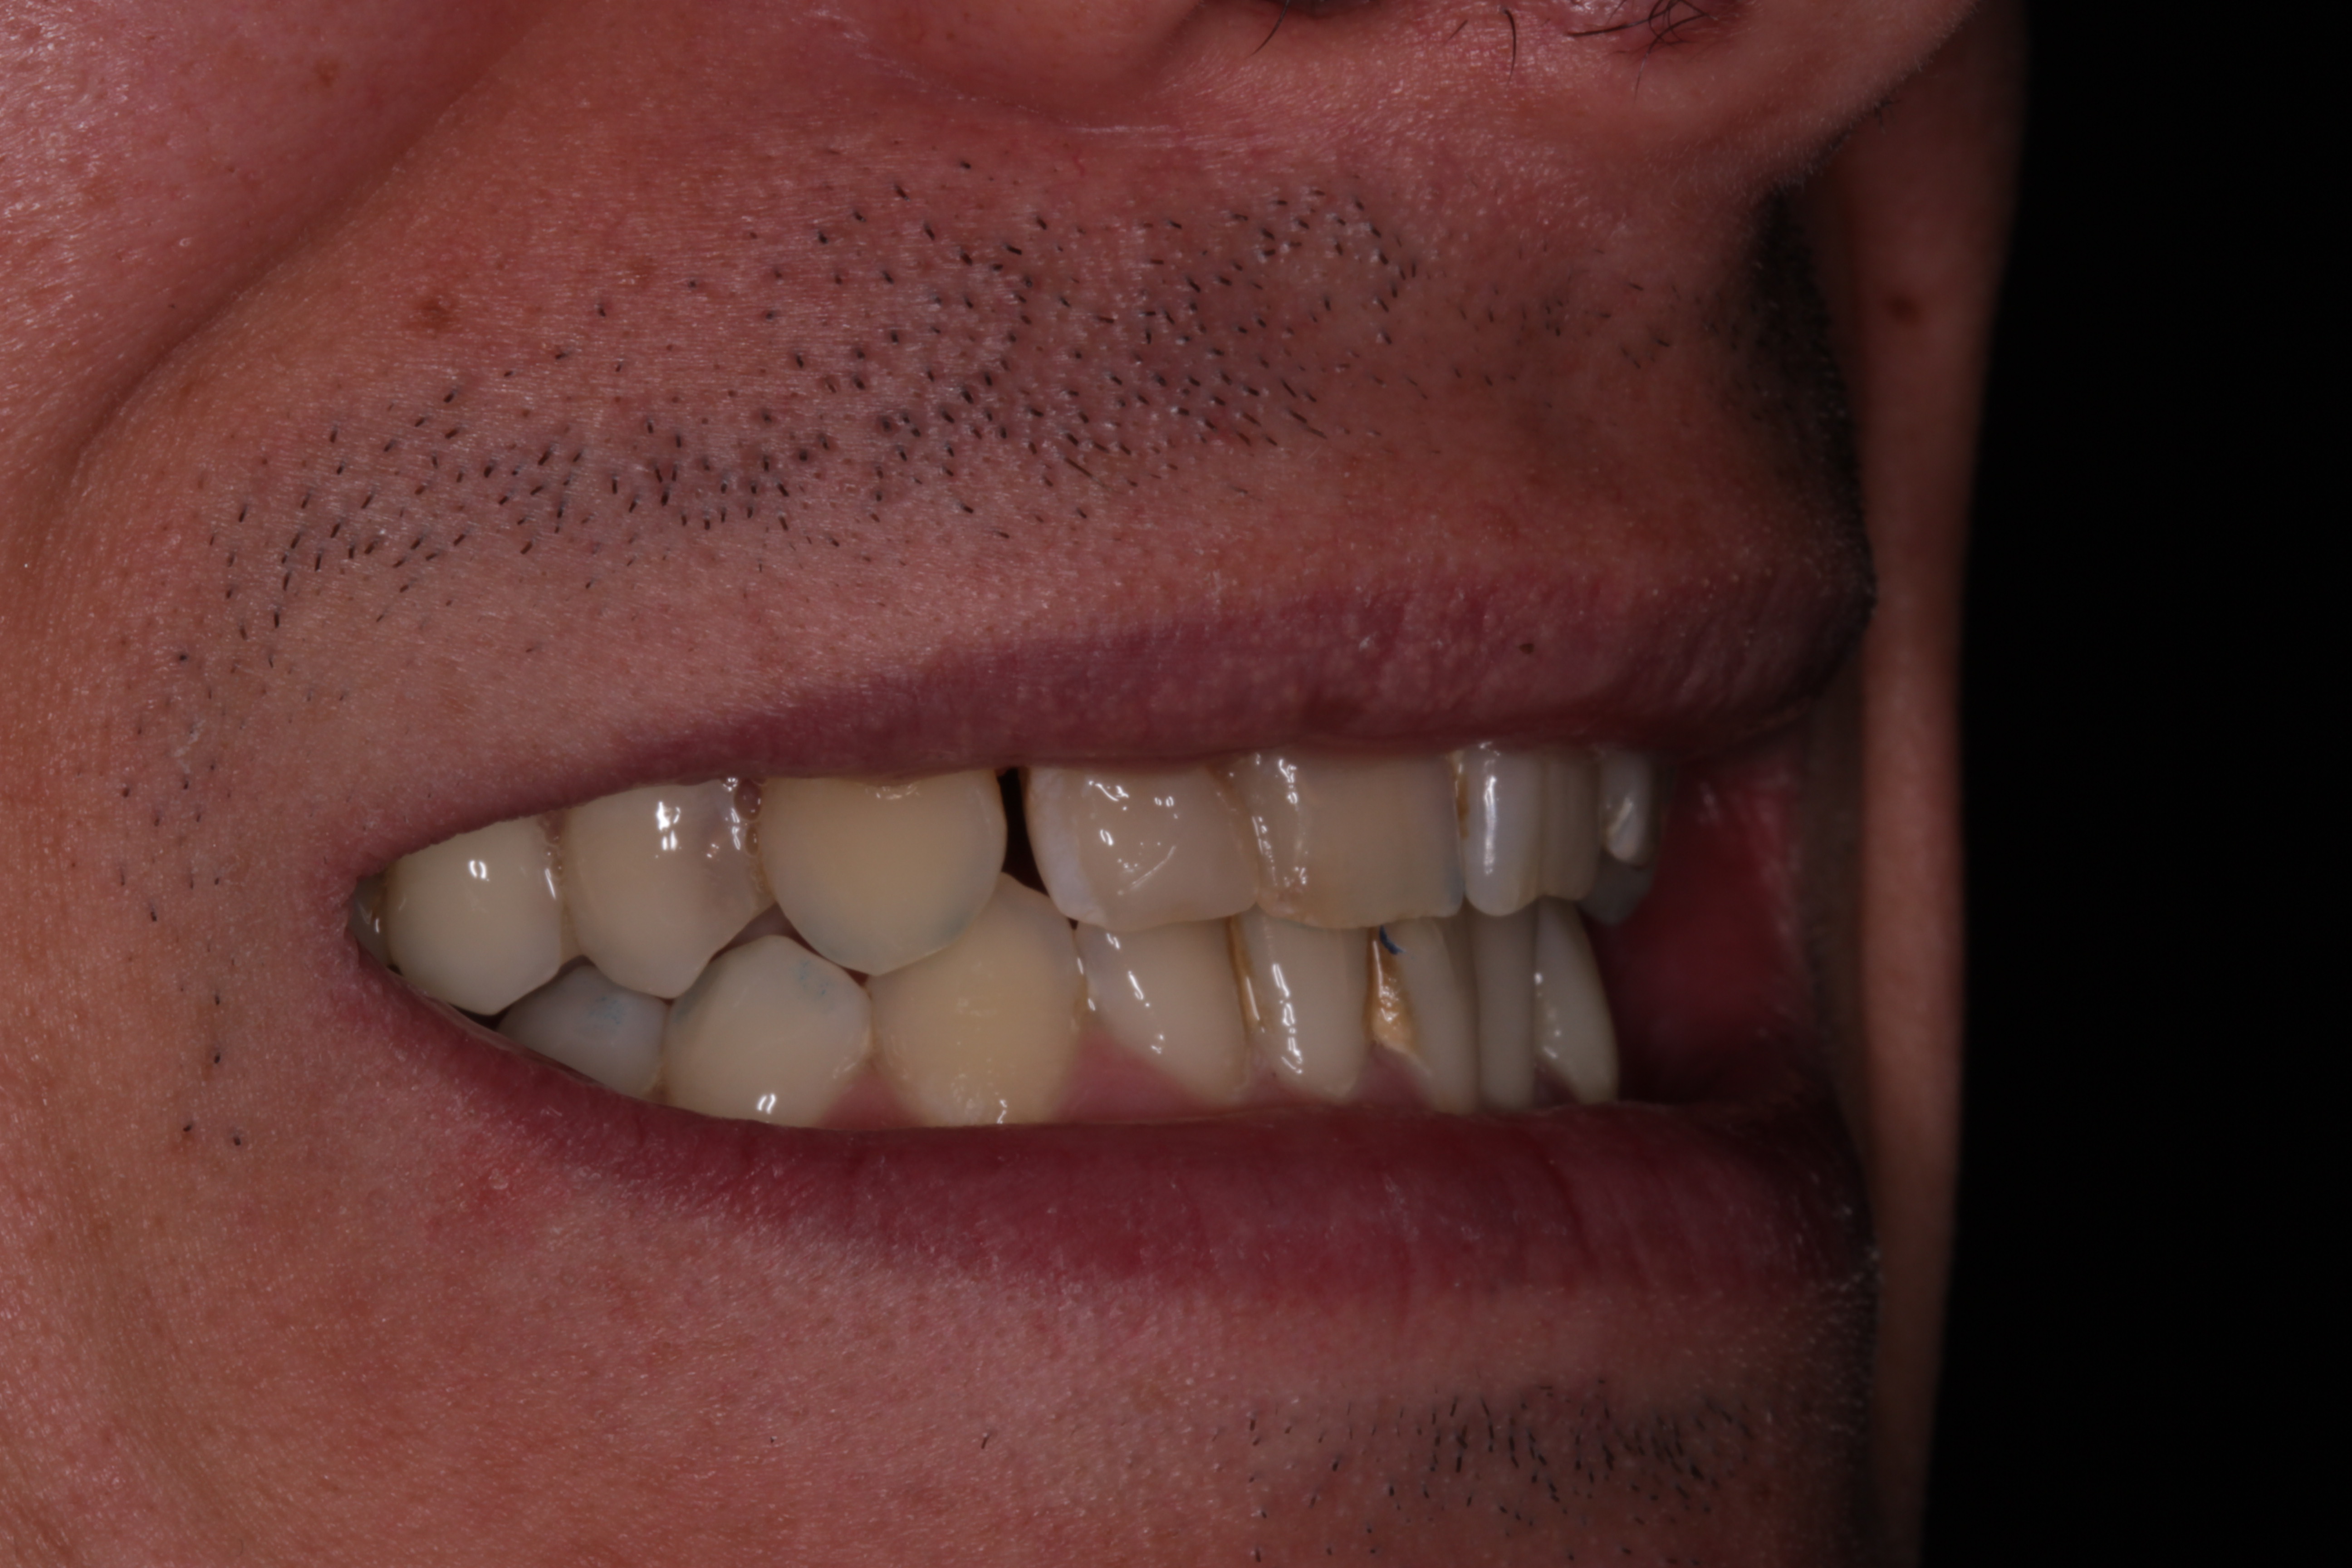

Alvaro Sánchez – 2024-2026 – CAS002

- Rehabilitación postraumática